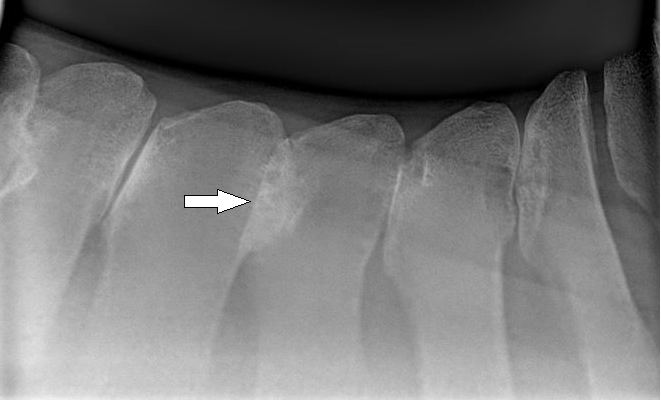

Now, have a look at the image below. You will notice that this X-ray shows an arrow pointing at an overlapping of bones. These spinous processes are touching (or kissing) each other along the horse's back. There is no room for comfortable movement, and the bones rub painfully together.